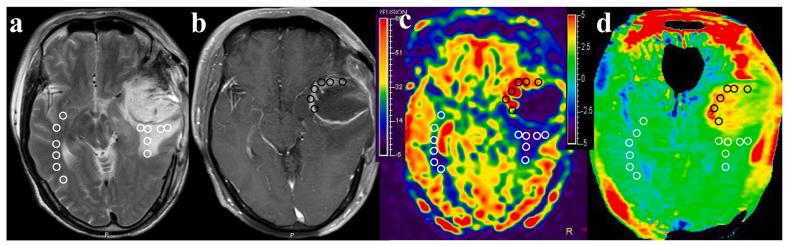

The management of tumor recurrence (TR) and radiation-induced brain injury (RIBI) poses significant challenges, necessitating the development of effective differentiation strategies. In this study, we investigated the potential of amide proton transfer-weighted (APTw) and arterial spin labeling (ASL) imaging for discriminating between TR and RIBI in patients with high-grade glioma (HGG).

The APTw and CBF values of TR were significantly higher compared to RIBI (P < 0.05). APTw MRI demonstrated superior diagnostic efficiency in distinguishing TR from RIBI (area under the curve [AUC]: 0.864; sensitivity: 75.0 %; specificity: 81.8 %) when compared to ASL imaging. The combined utilization of APTw and CBF value further enhanced the AUC to 0.922. The Delong test demonstrated that the combination of APTw and ASL exhibited superior performance in the identification of TR and RIBI, compared to ASL alone ( = 0.048).

APTw exhibited superior diagnostic efficacy compared to ASL in the evaluation of TR and RIBI. Furthermore, the combination of APTw and ASL exhibits greater discriminatory capability and diagnostic performance.